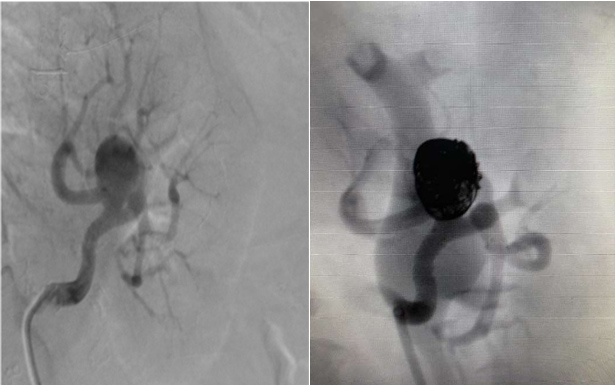

Neste boletim informativo, dr. Marcelo D´Anzicourt Pinto e dr. Guilherme Evangelista Rezende nos trazem revisão de literatura sobre a etiologia, apresentação clínica, diagnóstico por imagem, história natural e principalmente comentam os recursos atuais para intervenção não cirúrgica com materiais especificamente selecionados para tratamento percutâneo de aneurismas de artérias viscerais. Assim, dr. Marcelo mostrou caso de fechamento de aneurisma de artéria renal com técnica de utilização de Coil e Stent associadamente e que foi realizado no setor de Hemodinâmica da Santa Casa de Ribeirão Preto (SP). E o dr. Guilherme fez o tratamento intervencionista na Santa Casa de São Sebastião do Paraiso (MG) de grande aneurisma de artéria hepática utilizando outro tipo de dispositivo onde a oclusão do colo aneurismático garantiu a exclusão da grande dilatação vascular e garantiu a perviedade distal da artéria relacionada. Finalmente, dr. Antonione Lamartine faz completa análise das etiologias e das estratégias antitrombóticas em diferentes cenários clínicos onde a carga trombótica coronariana demanda abordagens individualizadas na sala de hemodinâmica bem como terapias fibrinolíticas adjuntas. Esperamos que tenham leitura informativa a sua prática clínica.

Aneurisma de Artéria Hepática